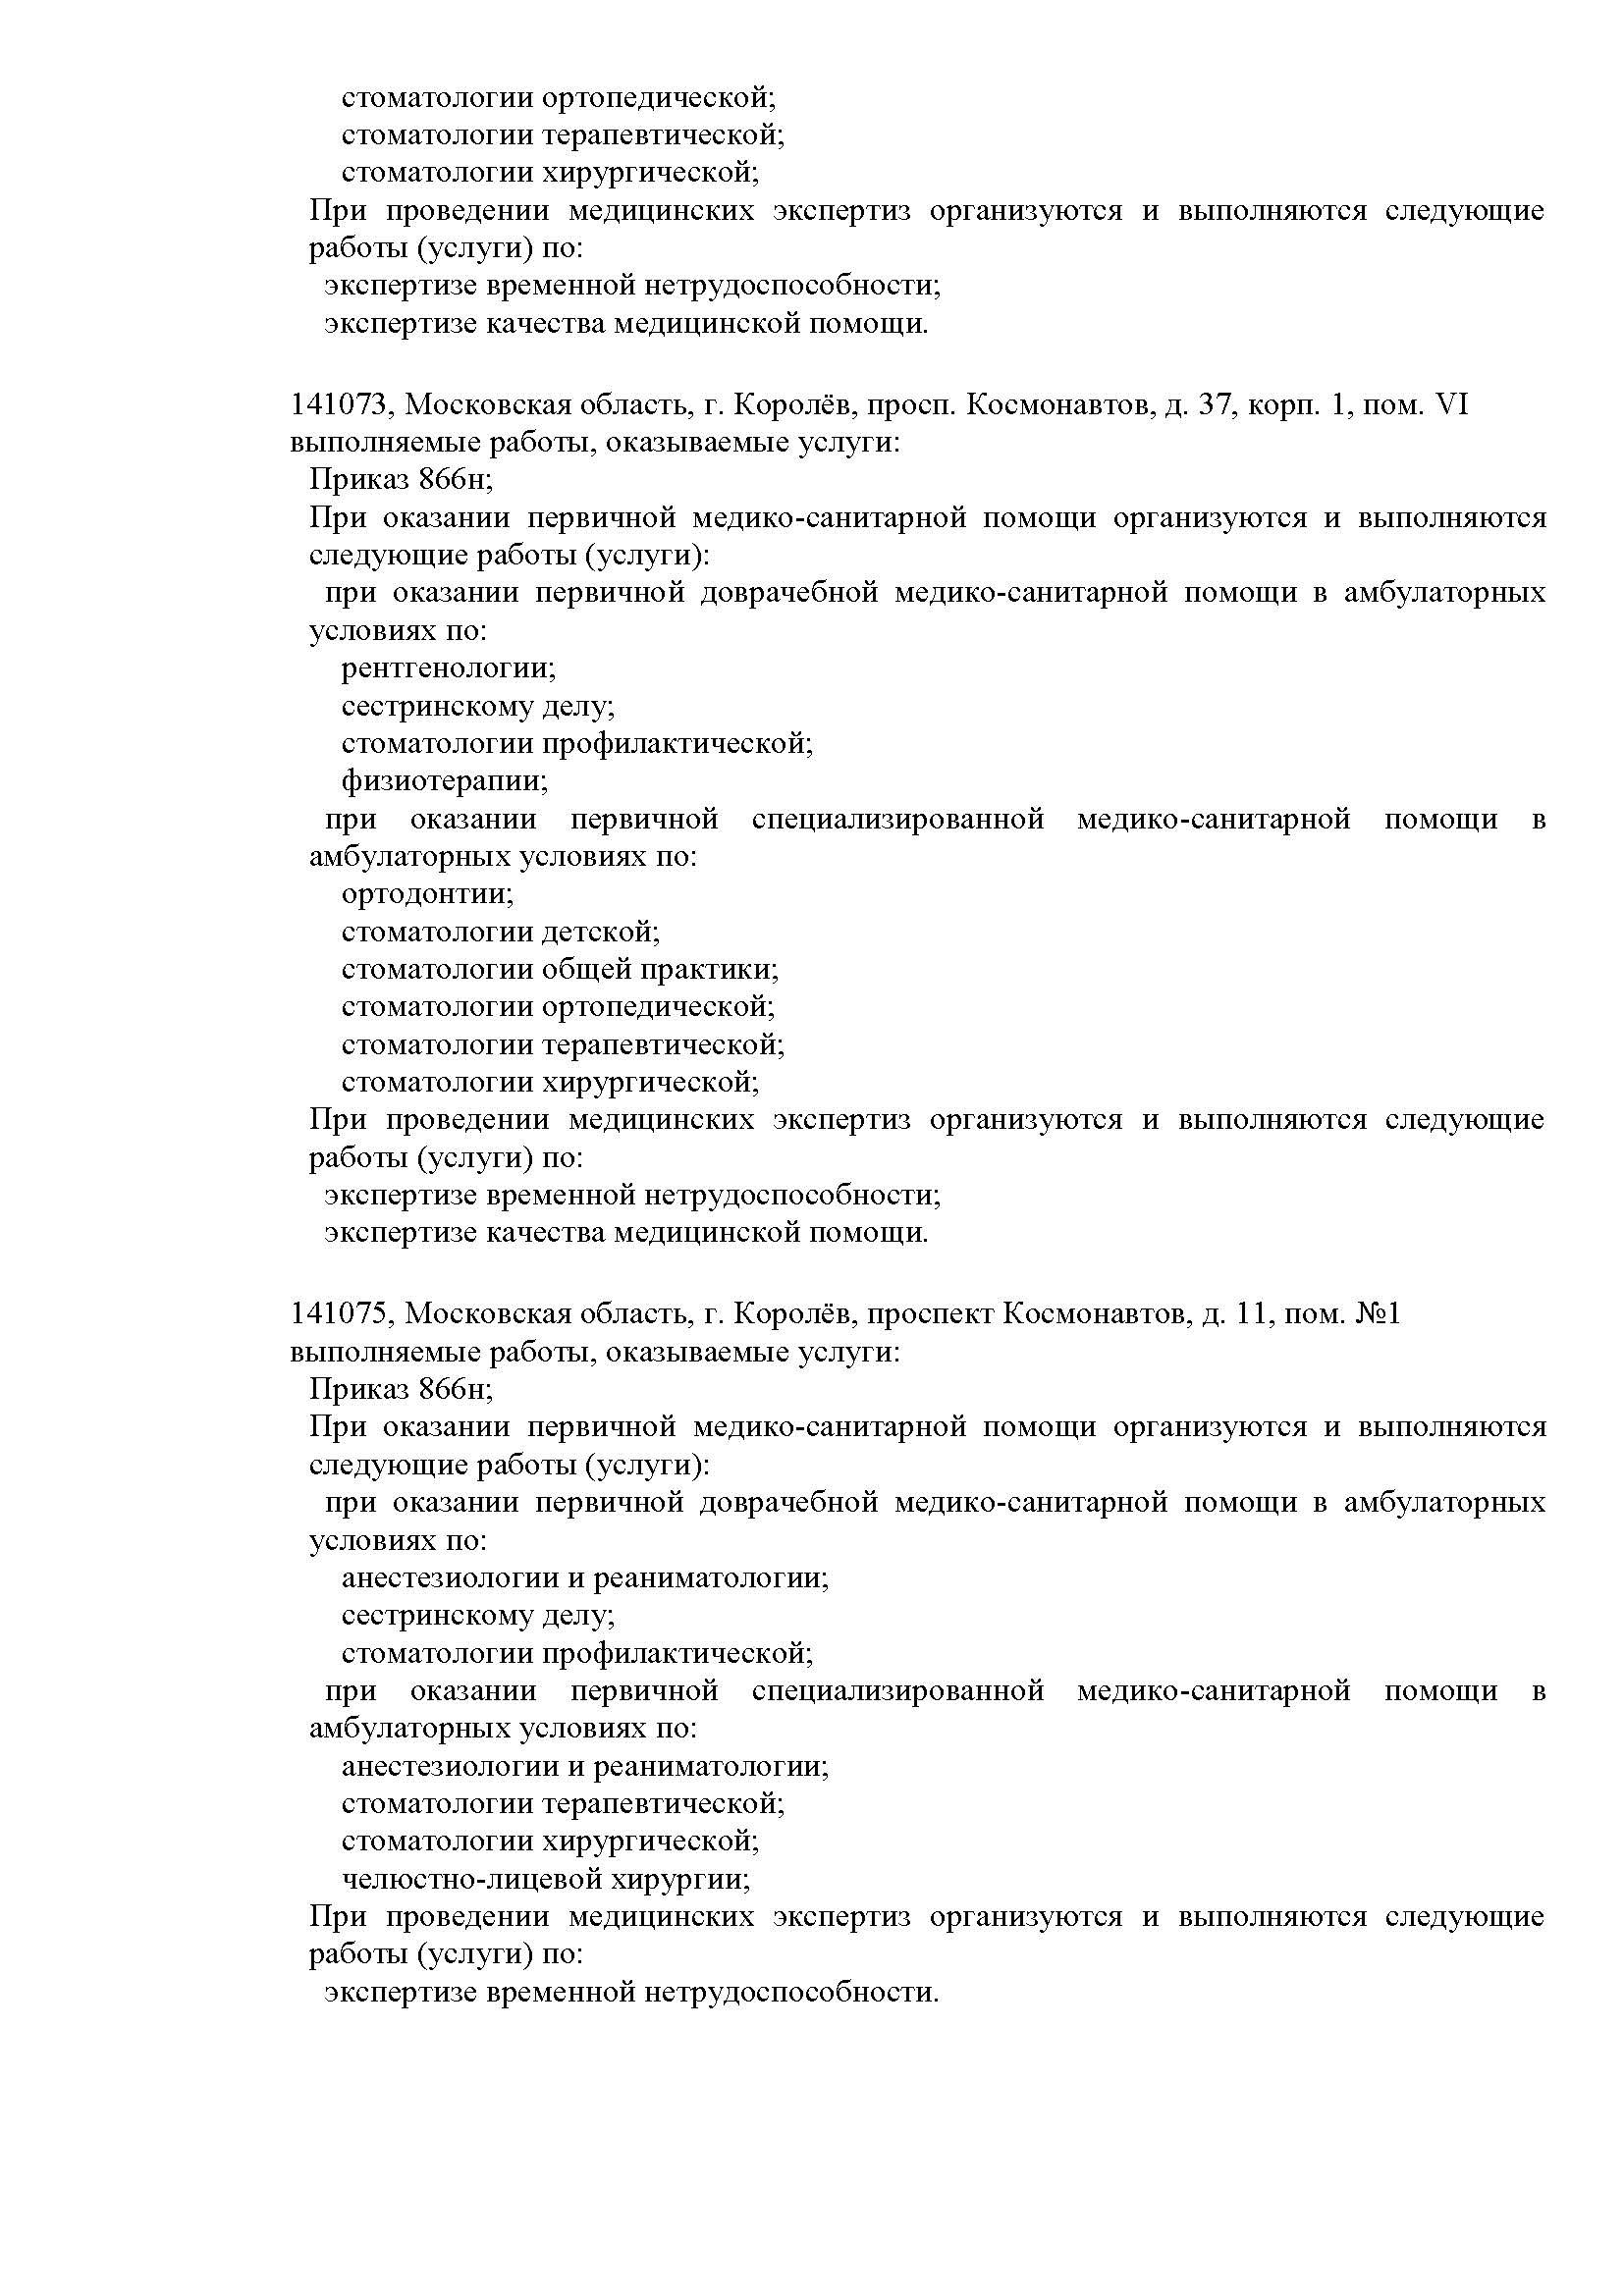

Наши лицензии